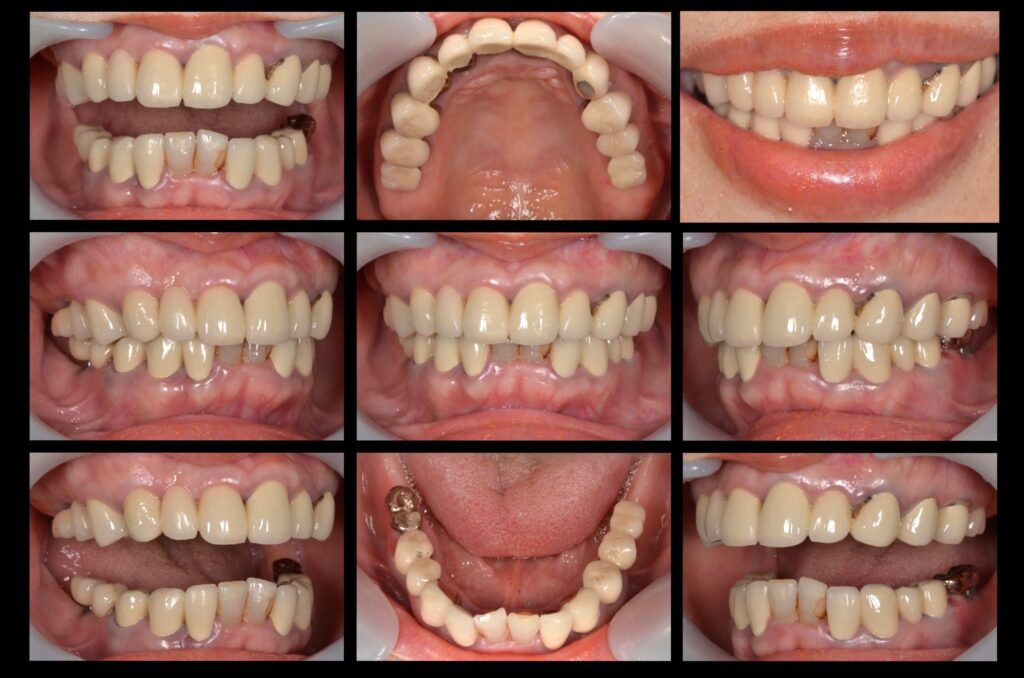

下の前歯が黒く見えて人前で笑えない。

浮くように噛み合わせが合わず、食事が不自由。

主訴の歯牙以外はメタルボンドクラウン(金属のフレームにセラミックが焼付いているクラウン)で補綴してあり、不透明なセラミックと経年変色した天然歯とのギャップが生じていました。

また、20年ぶりの歯科医院ということもあり歯の根やインプラント箇所に傷みが生じております。そして顎を全体的に評価すると主訴の下の前歯が歯列から飛び出し、下顎が食事や就寝時に動いたとき障害になっていることがわかりました。

患者様のご要望もあり、翌日より治療開始。見た目が気になるという気持ちはとても分かります。すぐに院内技工士が設計した綺麗な仮歯と入れ替えました。

人前での笑顔に自信がつき、食事は何でも食べられるので、今とても幸せです。

| 主訴 | 下の前歯が黒く見えて人前で笑えない、噛み合わせが合わず食事が不自由 |

| 診断名 | 不良インプラント・不正咬合・審美障害 |

| 年齢 | 60代女性 |